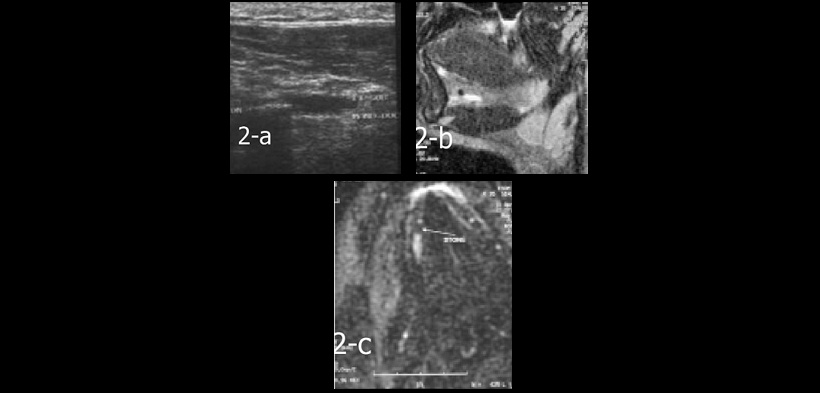

Fig. 2. a) Ecografía de la glándula submandibular derecha muestra un conducto dilatado y una imagen hiperecoica dentro de ella. La resonancia magnética del mismo caso muestra un conducto dilatado de la glándula submandibular derecha con presencia de un cálculo en su extremo, (b) vista sagital en T2, imagen ponderada muestra la presencia del cálculo. (c) sialograma RM, vista coronal muestra los mismos datos.